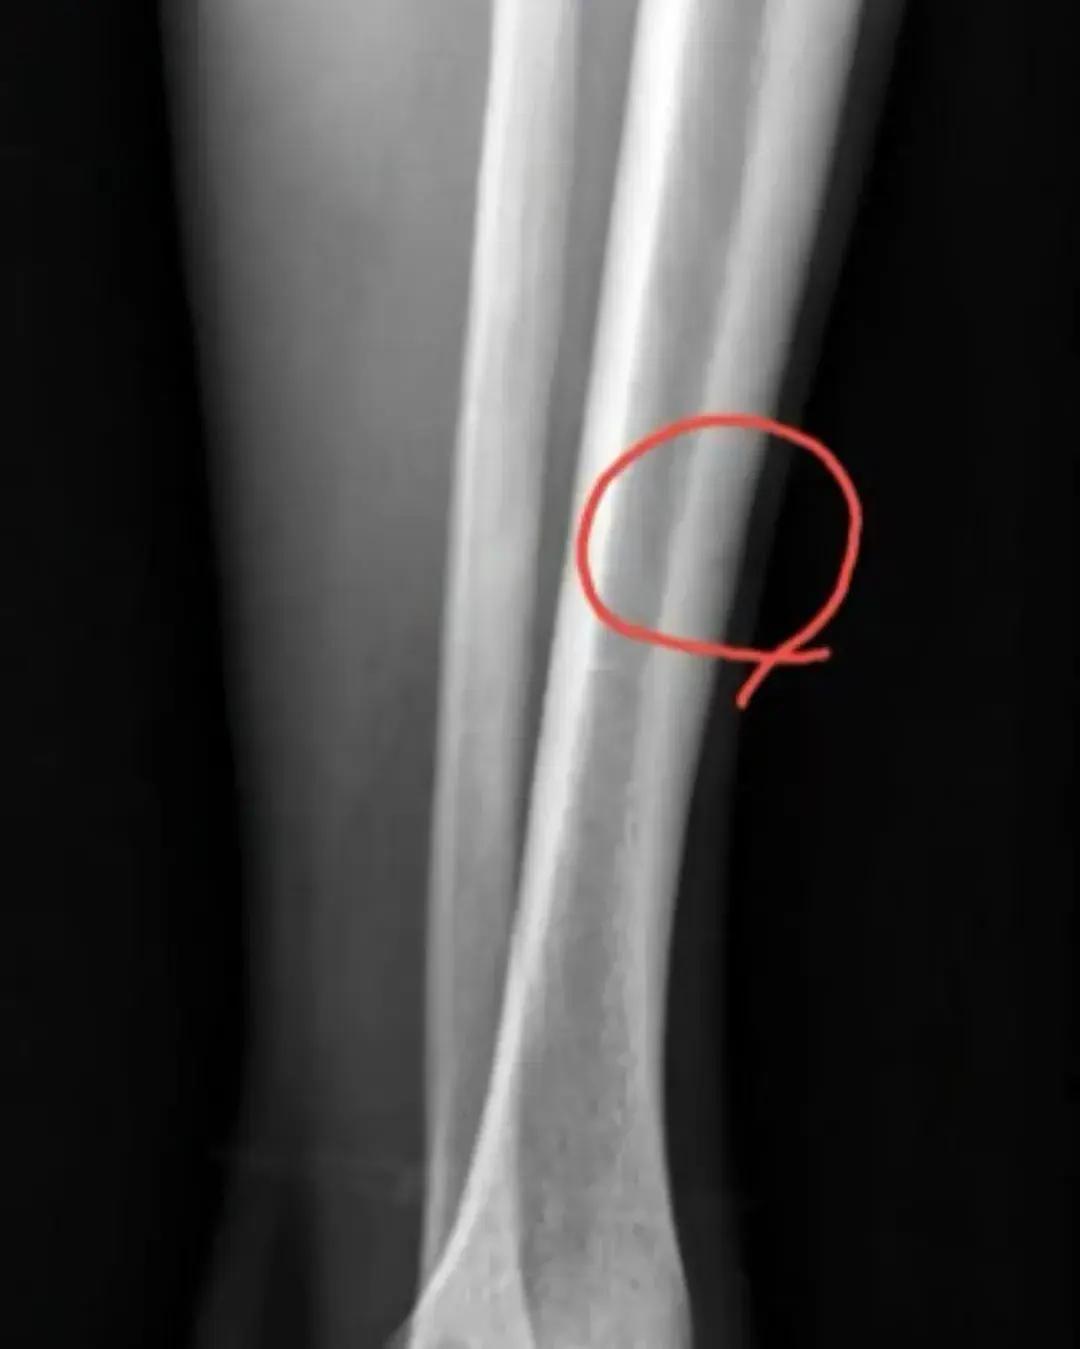

備受矚目的孫銘徽傷病情況,今天上午終於有了明確答案。就在剛剛,浙江廣廈核心球員孫銘徽,通過個人社交媒體賬號,向球迷分享了他的身體情況,從孫銘徽發佈的X光照片來看,他此次罹患的是左小腿輕微骨裂,屬於是長期疲勞導致的傷病。雖然不是什麼嚴重問題,不需要通過手術來治療,但由於小腿已經出現骨裂,因此孫銘徽也必須接受休息,給予小腿恢復充足的時間,距離季後賽開打還有兩個星期的時間,不知道他能否趕上今年季後賽的舞臺。